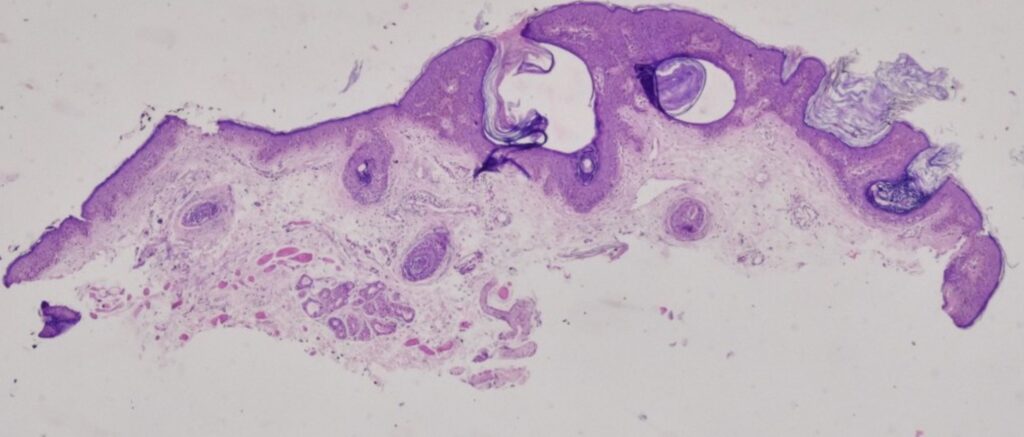

Tanto a la dermatoscopia como a la AP se ven pdeudoquistes corneos que orientan a una queratosis seborreica

Queratosis seborreica